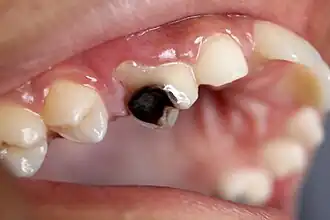

Destruction of a tooth by dental caries and disease

Montage of four pictures: three photographs and one radiograph of the same tooth.

(A) A small spot of decay visible on the surface of a tooth. (B) The radiograph reveals an extensive region of demineralization within the dentin (arrows). (C) A hole is discovered on the side of the tooth at the beginning of decay removal. (D) All decay removed; ready for a filling.